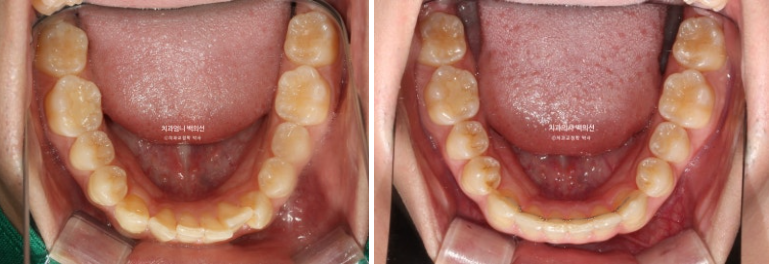

2022.10

송곳니가 많이 회전되어있고

송곳니를 포함한 앞니 치아들이 겹쳐져 있습니다.

22년 10월에서 24년 9월까지 1년 11개월간 79개의 장치를 모두 낀 후 모습입니다.